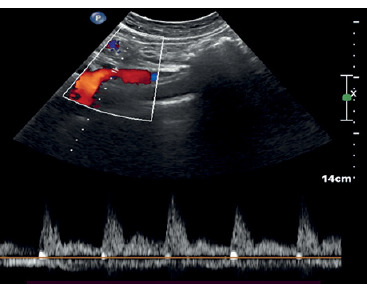

Aim: Our objective was to evaluate the role of a combination of both intestinal ultrasound (IUS) and colour Doppler with different parameters for monitoring changes in inflammation over time and to reveal their potential role in the assessment of response to biologic therapy in inflammatory bowel disease (IBD) patients.

Material and methods: Before the induction of biological therapy, IUS together with colour Doppler of the intestine was conducted. Response to therapy was defined following the international guidelines.

Results: A total of 45 patients with histopathological diagnosis of IBD were enrolled in the study. All patients received biological therapy and were assessed for response after 3 months. Out of those patients, 34 (75.6%) had good response while 11 (24.4%) failed to respond to the treatment. Our findings point to a strong association between bowel wall thickening (BWT) and serum albumin, erythrocyte sedimentation rate (ESR), and c-reactive protein (CRP). The overall sensitivity of IUS varied from 54 to 93% when evaluating bowel affection, with a specificity of 97-100%, in comparison to our results, which showed a sensitivity of 64-74% and specificity of 79-82%. Doppler parameters could predict the response to the biologic therapy in IBD patients.

Conclusions: Intestinal ultrasound and colour Doppler provide a safe, non-invasive way to monitor changes in inflammation and blood flow in the digestive tract.